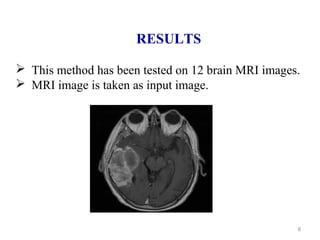

RESULTS

 This method has been tested on 12 brain MRI images.

 MRI image is taken as input image.